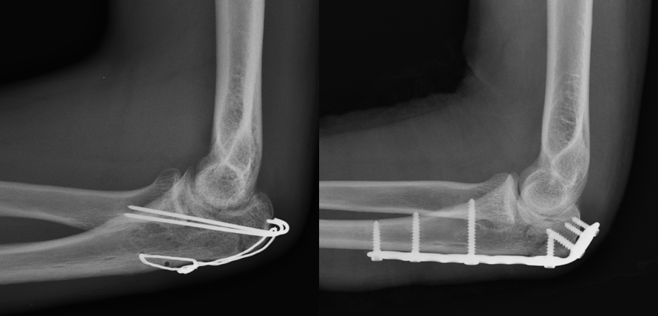

Cotovelo Uma Fratura Do Olecrano Pode Ser Segurada Com Placa E Parafusos Foto Premium